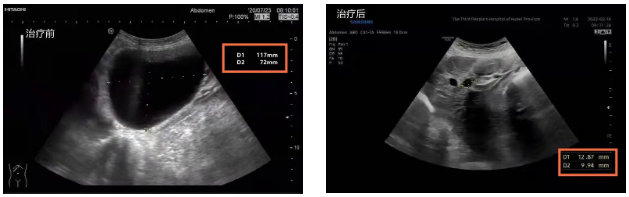

原来,80岁的李婆婆在一年前频繁出现右上腹胀痛不适,为了查明原因,李婆婆来到了湖北省第三人民医院(湖北省中山医院)中西医结合肝病科就诊。完善检查后结果提示,婆婆的肝脏上长了一个11.8cm×7.2cm的巨大囊肿,这也是其右上腹胀痛以及转氨酶升高,肝功能异常的主要原因。

消除顾虑后的李婆婆欣然接受了治疗,术后囊肿缩小到1.3cm×1.0cm,治疗后为了防止囊肿复发,刘黎明主任根据李婆婆的体质应用中药辩证施治,术后随访1年,囊肿持续缩小,原本巨大的囊肿变得只有花生米大小,肝功能也恢复正常,于是就出现了开头的一幕。